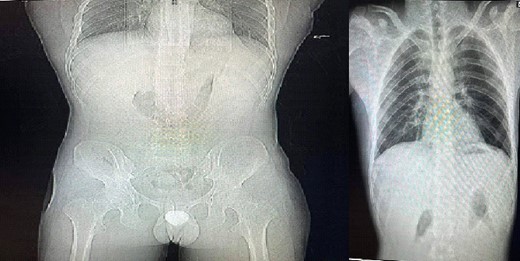

Chest X-ray and standing abdominal X-ray revealed pneumoperitoneum (Fig. 3).